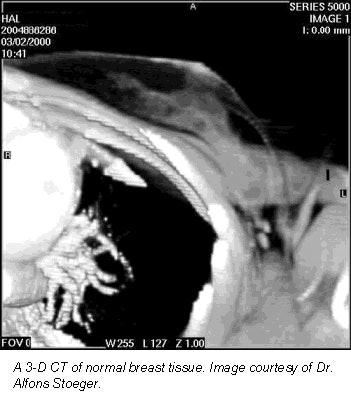

Is it possible to assess breast tissue with 3-D CT on patients who are already undergoing routine multislice spiral CT chest exams? Austrian researchers conducted a preliminary study on 20 patients at the Innsbruck University Hospital and found the modality was adept at pinpointing certain types of breast pathology.

"On the other hand, we know that 3-D real-time volume rendering has been applied in many regions of the body. Our goal was to extract maximum information for breast pathologies from routine multislice spiral chest CT without further examination or radiation exposure to the patient, simply by post-processing the existing data," he explained.

A Somatom Plus 4 Volume Zoom (Siemens Medical Solutions, Iselin, NJ) was used. The images were reconstructed to 3-mm slice thickness at 2-mm increments. The data was then volume-rendered with Siemens 3-D Virtuoso software.

The breast images were assessed using an interactive change of rendering parameters, zooming, color encoding, and clip-plane editing in different orientations. "Clip planes can be placed in any orientation," Stoeger explained. "When placed in the oblique plane, you can acquire images that are similar to mammograms."